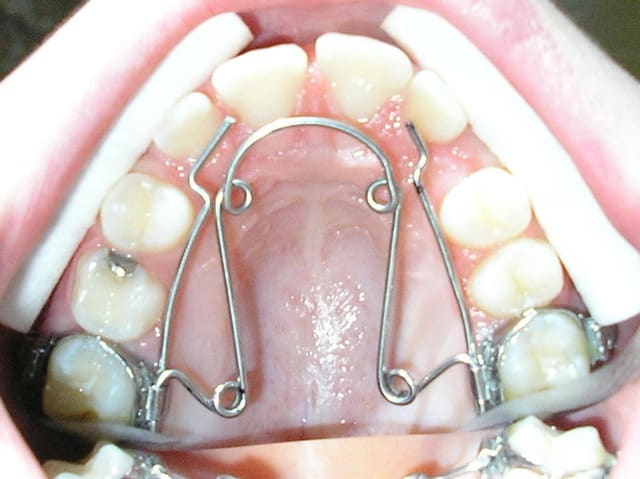

pour faire suite à la question de bjc les incisives maxillaire ont une taille normale de 9 mm, voici la pano et une photo du maxillaire aujourd'hui.

Bref, le systeme de MacAndrews peut etre utile dans ces cas. Un arc de base de stabilisation basic, jambe du cote de la deviation contre la laterale, le cote oppose est a distance pour permettre le mouvement des 4 incisives. Une boucle au milieu du pont lateral sert de stop pour le ressort active de la quantite de deplacement desiree avec 3 mm de plus et insere pendant la fabrication de l'arc de base. On laisse faire le systeme tout seul.